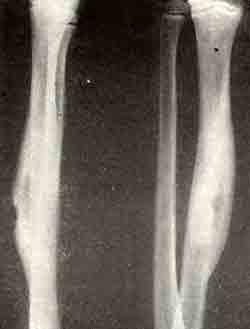

Изолированный абсцесс большеберцовой кости

Изолированный абсцесс большеберцовой кости, симулировавший остеоид-остеому, результат через 19 месяцев после консервативного лечения.